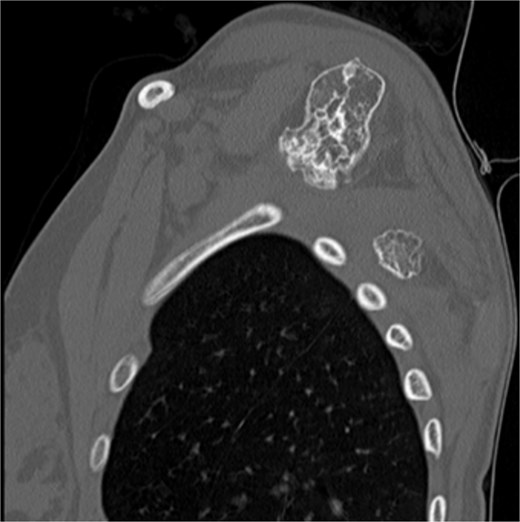

The imaging investigation was initiated by our department, as we were clinically suspicious of the presence of osteochondromas, due to the history of HME in both patients. Both patients were subscribed an anteroposterior X-ray of left shoulder and a CT scan for pre-operative planning. Also, radiographic evaluation of both knees and left forearm were taken and revealed multiple exostoses as a part of the HME follow-up that both girls underwent. The CT scan of the 14 year old patient demonstrated three bony lesions arising from the ventral aspect of left scapula. The largest one extruded from superior angle heading medially to the vertebral bodies. The other two smaller arose one from the lateral angle and one from the inferior angle. The CT scan of the 9 year old patient revealed one bony lesion arising ventrally from the superior angle of the left scapula heading medially as well (Figs 2 and 3). The diagnosis of VSO was made in both cases.

CT of the 14-year-old patient showing both lesions in sagittal plane.